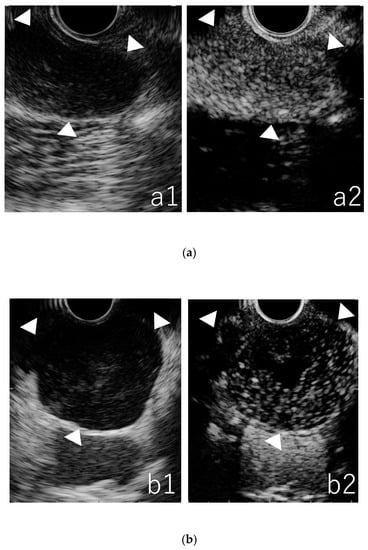

3.3. Qualitative Evaluation in CE-EUS

3.4. Quantitative Evaluation in TIC